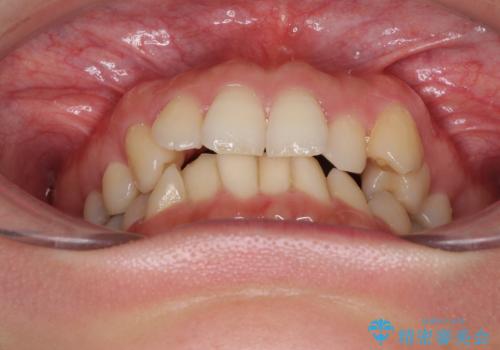

- 上下の前歯のデコボコを治したいとのことで来院された患者様です。

仕事柄、アジアの3つの国と地域を行き来するため、ワイヤー装置での治療は難しいと考えられました。

上下顎ともにIPR(歯と歯の間を削る)と歯列全体の拡大によって叢生が解消するように設計し、インビザラインにより治療を行うこととしました。